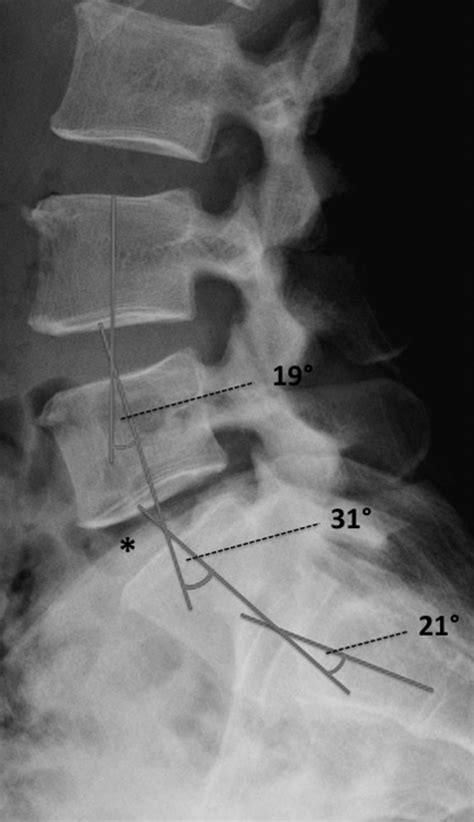

• Spondylolisthesis: This condition involves the forward slippage of one vertebra over another, often occurring at the L5-S1 level. It can cause significant pain and neurological symptoms, including sciatica.

The lumbosacral transitional segment is particularly vulnerable to injuries in athletes and individuals who engage in high-impact activities. Sports such as football, weightlifting, and gymnastics can place significant stress on this region, leading to conditions such as spondylolysis and spondylolisthesis. Understanding the biomechanics of the lumbosacral region is essential for preventing and managing sports-related injuries.

Spondylolysis is a condition characterized by a defect or fracture in the pars interarticularis, a small bone in the vertebrae. This condition is common in athletes who engage in repetitive hyperextension of the spine, such as gymnasts and football linemen. Spondylolisthesis, the forward slippage of one vertebra over another, can occur as a result of spondylolysis or other degenerative changes in the spine.

Advances in technology have significantly improved the diagnosis and treatment of conditions affecting the lumbosacral transitional segment. Imaging techniques, such as MRI and CT scans, provide detailed visualizations of the spine, allowing for accurate diagnosis and treatment planning. Surgical techniques, such as minimally invasive procedures, offer less invasive options for addressing structural issues in the spine.

Imaging techniques, such as MRI and CT scans, provide detailed visualizations of the spine, allowing for accurate diagnosis and treatment planning. These techniques can reveal degenerative changes, herniated discs, spinal stenosis, and other abnormalities. Surgical techniques, such as minimally invasive procedures, offer less invasive options for addressing structural issues in the spine. These procedures can reduce recovery time, minimize scarring, and improve outcomes.